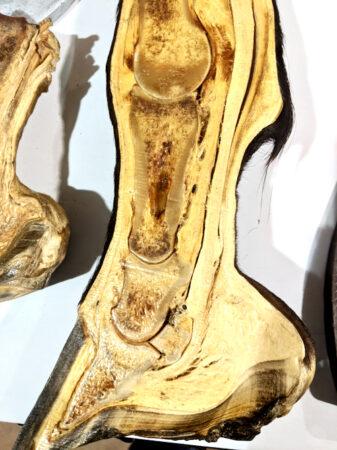

Here are some anatomy photos:

Can you spot the DDFT running under the navicular and connecting to the coffin bone?

The hoof on the right has laminitis with rotation of the coffin bone. The hoof on the left is normal.